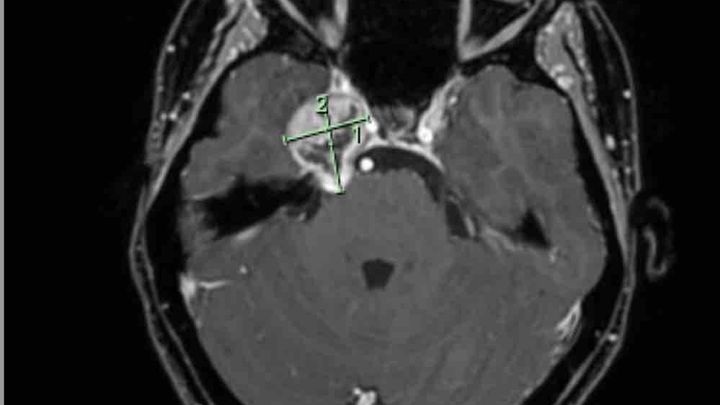

I found out I have Trigeminal Nerve Schwannoma for those who don’t know what this is, it’s a rare skull based Tumour. It’s located on my Trigeminal nerve causing debilitating Headaches, double vision and pins and needles on the right side of my face where my tumour is located. I am thankful & feel like I have won the lotto daily due to the fact that these types of tumours are mainly “benign” meaning they aren’t cancerous. It doesn’t take away how scared I feel, how anxious I am about everything medical, how my anxiety is through the roof, the panic attacks and I know that I have a long way of recovery not only mentally but physically with my road of recovery ahead.